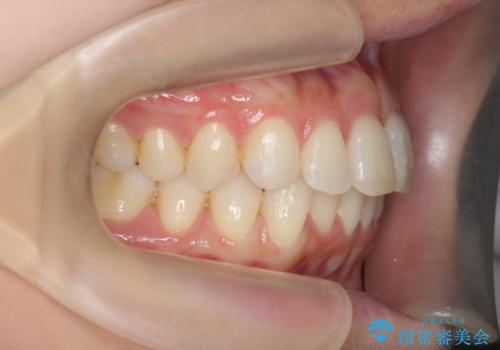

昔ワイヤー矯正をして後戻りした 軽度のがたつき モニター矯正

- 矯正治療後の後戻りを主訴に来院。

特に下の前歯のがたつきを気にされていました。

マウスピース矯正で再矯正を行いました。

再度の後戻りを防ぐため、下顎前歯の裏にはワイヤーを貼る保定を行っています。